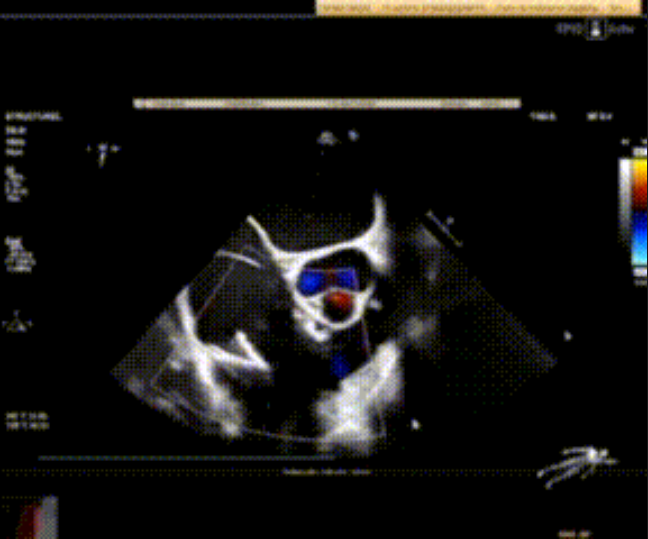

術(shù)前心臟超聲提示:極重度三尖瓣返流,右房容積明顯增大,三尖瓣瓣環(huán)顯著擴張。

術(shù)后心臟超聲提示:LuX-Valve Plus植入后,三尖瓣瓣環(huán)處可見人工瓣膜回聲,未見返流,人工瓣膜穩(wěn)定,瓣葉開閉良好,連續(xù)多普勒估測三尖瓣平均跨瓣壓差僅為1mmHg。